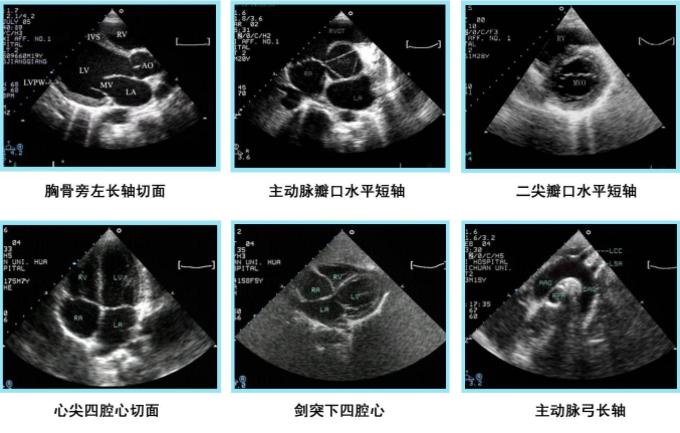

B型超声成像系统:又称超声断层法,或灰阶超声成像,目前应用Z广。光点显示,亮度随回声信号变化,深度扫描为垂直方向,位移扫描为水平方向,构成切面显示图。